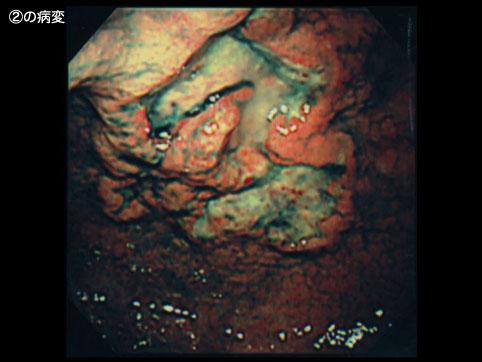

疾病(病理主体)的分类恶性淋巴系肿瘤/恶性淋巴瘤

部位(按器官分)胃(部位)/穹窿

检查方法内窥镜

肿瘤最大直径40以上

多发性肿瘤(同一器官)有(同时性)

多重性肿瘤(多个器官)有(同时性)